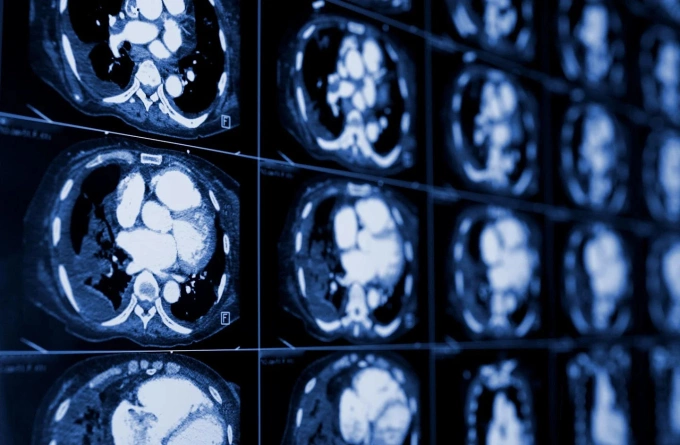

Ung thư phổi cướp đi sinh mạng hàng triệu người toàn cầu mỗi năm, song phẫu thuật robot và những tiến bộ điều trị đang đem lại cơ hội sống cao hơn cho các bệnh nhân.

Tại Việt Nam, ung thư phổi là nguyên nhân tử vong do ung thư cao thứ hai sau ung thư gan, với khoảng 22.500 ca tử vong mỗi năm, chiếm gần 19% tổng số. Dù các phương pháp điều trị đã có nhiều tiến bộ, thực tế cho thấy đa số bệnh nhân được chẩn đoán ở giai đoạn muộn, khiến tiên lượng sống còn không cao.